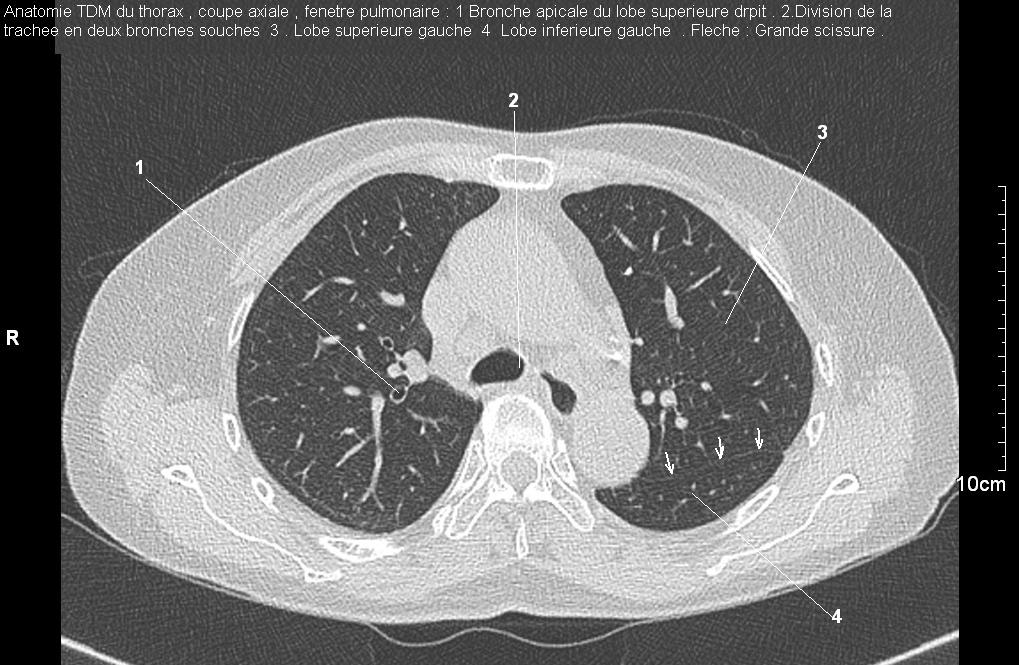

Radioanatomie pulmonaire ( image radiologie thoracique normale )- La Tomodensitometrie du  thorax ( coupes axiales fenetre pulmonaire )

Les fenetres parenchymateuses permettre d'etudier anatomie du poumon et juger sur les lesions du parenchyme pulmonaire en coupes axiales de 0,5-1cm sur le thorax .